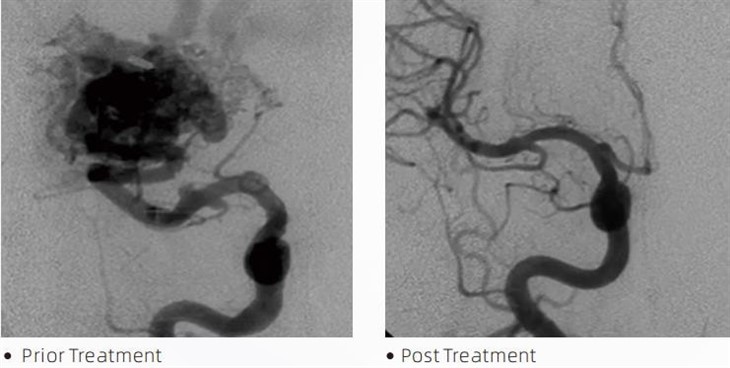

LavaTMembolik elim miya anevrizmasi, arteriovenoz malformatsiyalar va o'smalar kabi holatlarni davolash uchun minimal invaziv muolajalar paytida interventsion neyroradiologlar tomonidan qo'llaniladigan tibbiy asbobdir. Lava embolik elim xavfsizlik, foydalanish qulayligi va samaradorlik nuqtai nazaridan tibbiyot mutaxassislari va bemorlarga bir qator afzalliklarni taqdim etadi. Lava qon tomirlarini tez va samarali tarzda yopishga qodir. Jarayon elimni to'g'ridan-to'g'ri maqsadli idishga kiritishni o'z ichiga oladi, u erda polimerlashadi va anevrizma yoki malformatsiyani to'ldiradigan quyma massaga qattiqlashadi. Keyin u lezyonga qon oqimini samarali ravishda to'xtatadi, uning yorilishining oldini oladi va doimiy shikastlanish yoki qon tomir xavfini kamaytiradi. Lava tarkibiga lava-12, lava-18 va lava-34 kiradi. Har bir formula maxsus klinik ehtiyojlarni qondirish uchun mo'ljallangan. Lava-18 umumiy foydalanish uchun standart formuladir. Lava-34 - yuqori oqimli tomirlar uchun yuqori yopishqoqlikdagi elim. Lava-12 esa pastroq qovushqoqlikka ega va ko'proq oquvchan bo'lib, distal mikrotomirlar paydo bo'lishiga imkon beradi. Ushbu variantlar yordamida interventsion neyroradiologlar optimal natijalarni ta'minlash uchun mos Lava formulalarini tanlashlari mumkin. Lavaning eng ajoyib xususiyatlaridan biri uning yopishqoq bo'lmagan xususiyatlaridir. Ushbu modda maqsadli hududga yetguncha barqaror turishi uchun maxsus ishlab chiqilgan. Bu xususiyat shuni anglatadiki, lava embolik elim arteriya ichiga to'g'ri joylashtirilishi va u erda atrofdagi to'qimalarga yopishmasdan yoki bog'lanmasdan qolishi mumkin.